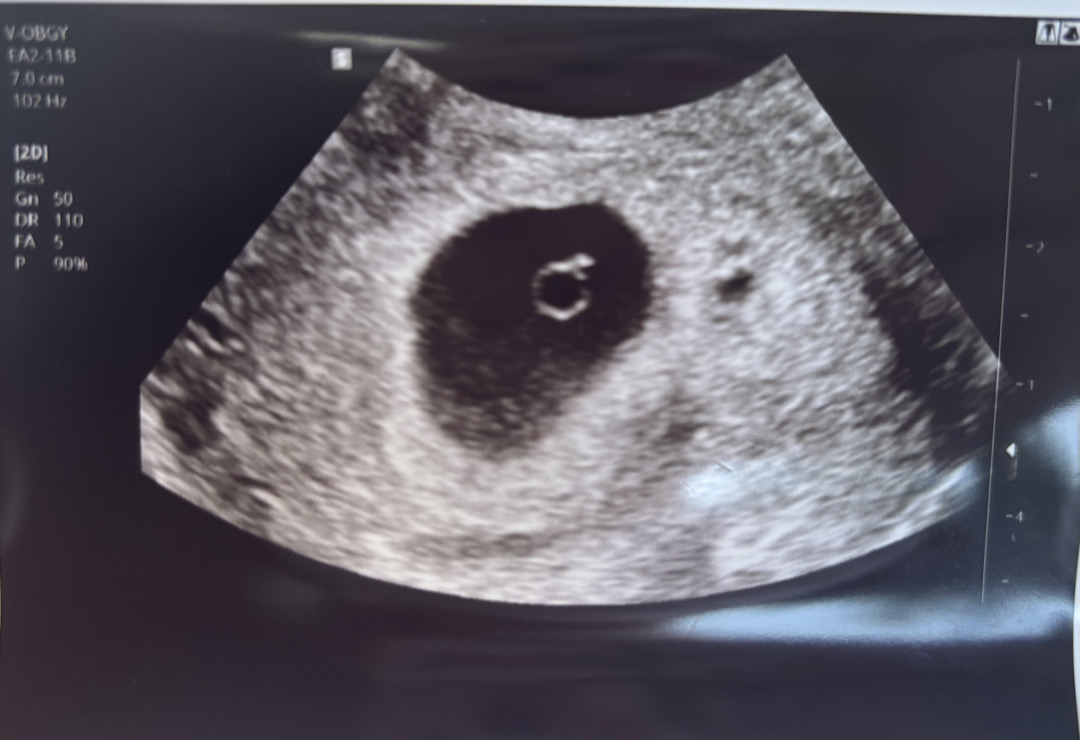

5주차 난황

막생 5월 27일 오늘 기준 6월 2일차인데, 다른분들보다 일주일정도 주수가 늦어서 이제 5주차네요 배란일 등 이슈로 초기에는 2주정도까지도 차이가 난다고 하더라구요 근데 초음파 봤는데 아기집 크기를 안재어주시는데, 요청하면 재어주시나요..?